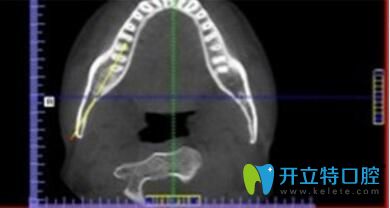

? 1、詳細(xì)測(cè)量數(shù)據(jù):

? 采用診療標(biāo)準(zhǔn),在制定精細(xì)的矯正方案前,必須通過數(shù)字化診療,集全景,頭顱、CBCT功能于一體,能夠精準(zhǔn)定位頭顱數(shù)據(jù)采集,提供高清晰度3D診斷圖片,采集口腔全景數(shù)據(jù),提高治療效果,因此牙齒將準(zhǔn)確的向設(shè)計(jì)好的方向移動(dòng),呈現(xiàn)更美的口腔弧度。

長(zhǎng)沙美萊口腔牙齒矯正優(yōu)勢(shì)詳細(xì)測(cè)量數(shù)據(jù)